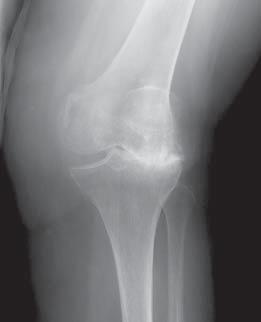

Joint cartilage is a tough, smooth tissue that covers the ends of bones where joints are located. It helps cushion the bones during movement, and because it is smooth and slippery, it allows for motion with minimal friction. Osteoarthritis, the most common form of arthritis, is a wear-and-tear condition that destroys joint cartilage. Sometimes as the result of trauma, repetitive movement, or for no apparent reason, the cartilage wears down, exposing the bone ends. This can occur quickly over months or may take years to occur. Cartilage destruction can result in painful bone-on-bone contact, along with swelling and loss of motion. Osteoarthritis usually occurs later in life and may affect only one joint or many joints.

A knee replacement is really a bone and cartilage replacement with an artificial surface. The knee itself is not replaced, as is commonly thought, but rather an implant is inserted on the bone ends. This is done with a metal alloy on the femur and plastic spacer on the tibia and patella (kneecap). This creates a new, smooth cushion and a functioning joint that can reduce or eliminate pain.